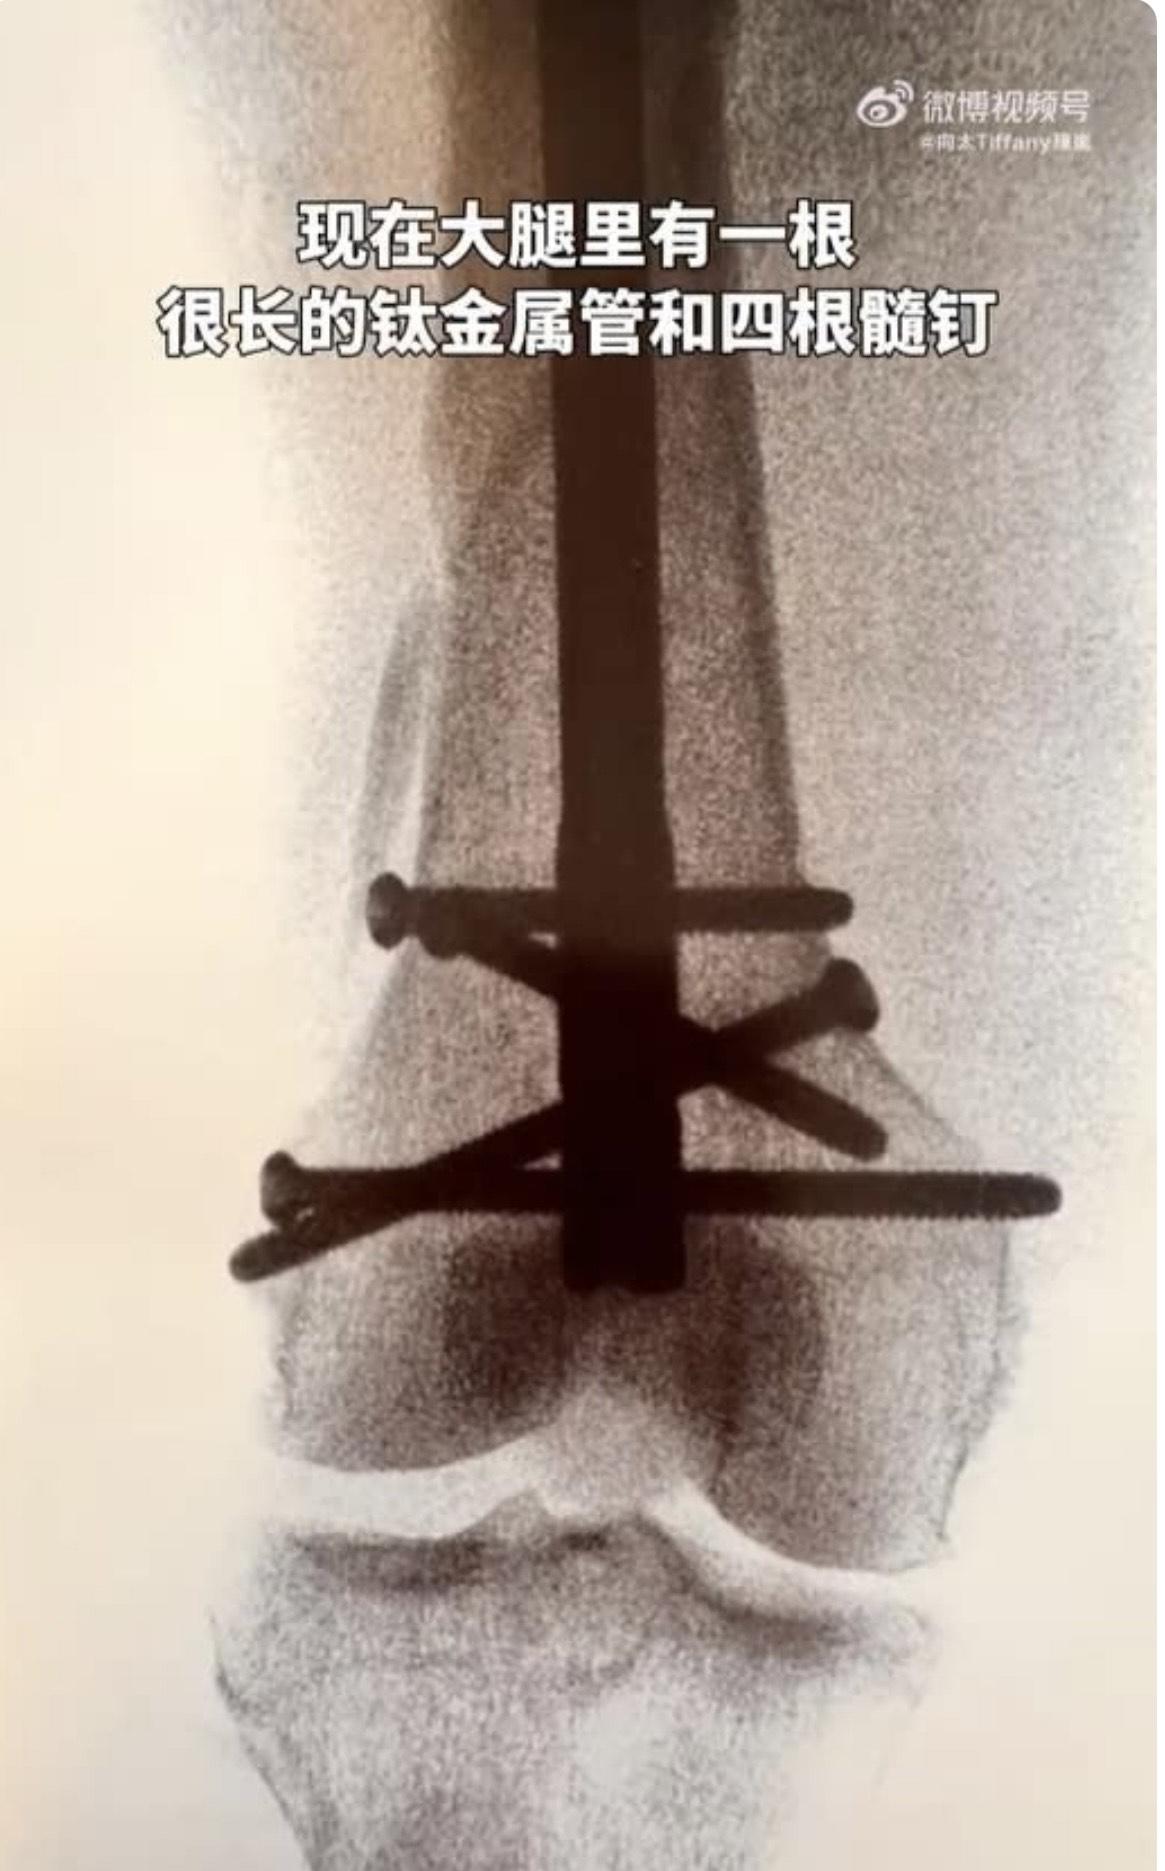

向太續透露,入院檢查後發現是大腿骨斷裂,進行微創手術從晚上10點開始,直至第二日凌晨3點半才結束,手術足足做了5.5小時;向太直言回到病房1小時後又開始痛,打了兩次止痛針,整晚只睡了1小時,但整個過程她卻非常勇敢,沒有流一滴眼淚。向太表示現時大腿有1根很長的鈦金屬管和4根髓釘,並自嘲是「鋼鐵女俠」。